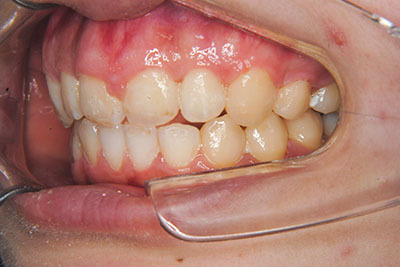

おとなの方でも矯正治療をあきらめないでください!

子供の頃に矯正治療を行う方が治療期間が短く済むというのは、確かですが、矯正治療は患者様の意識も重要です。

いくら歯が動き易くとも、本人がやる気でなければ効果は出ませんし、むし歯発生のリスクも高まります。おとなの方は顎の成長が終わっているため、治療の計画が立てやすいとも言えます。「もう大人だから…」とあきらめず、一度ご相談ください。